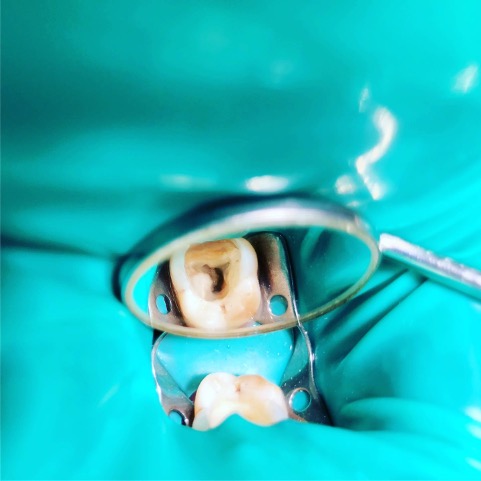

Un trattamento endodontico consiste nel salvare un dente compromesso da carie, traumi o fratture rimuovendone polpa e nervi infetti/infiammati responsabili di dolore, ascessi, cisti e granulomi.

Un adeguata endondonzia serve per salvare quei denti che altrimenti sarebbero destinati ad essere estratti. Quando un dente viene devitalizzato viene privato della sua irrorazione sanguigna e del nutrimento, rendendo la sua struttura più “vetrosa” quindi più fragile e soggetta a fratture. Per questo motivo è consigliabile nella maggior parte dei casi capsulare i denti una volta che hanno perso la loro vitalità.